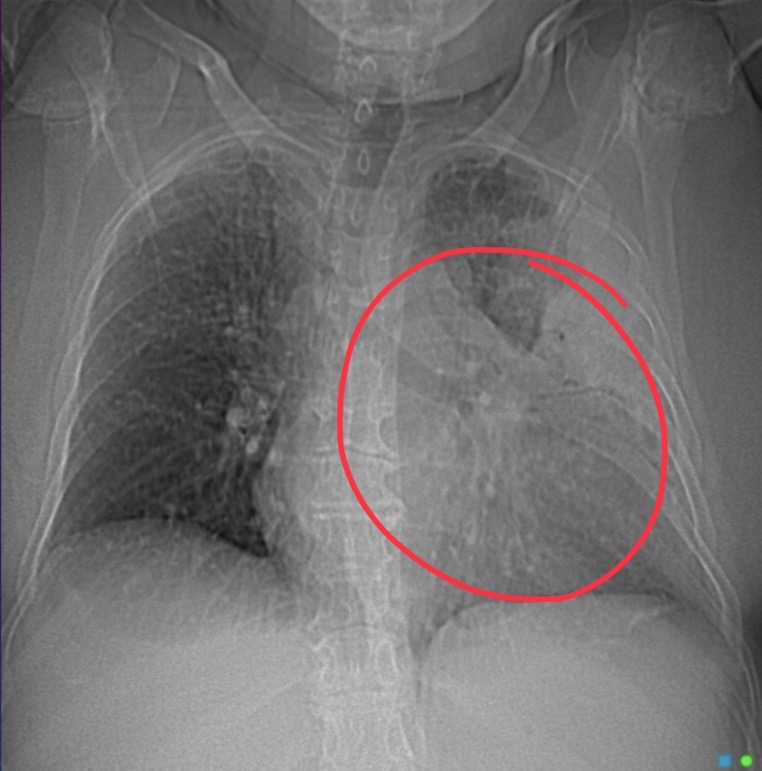

65-year-old female presented with one week history of difficulty passing urine, constipation, and back pain. Patient was found to be in a hyponatremic hyperosmolar and euvolemic state. Serum osmolality is low but urine osmolality is high, urine sodium is high. Pt suspected to have SIADH. no respiratory sx, no smoking hx or fhx of ca.

Non small cell lung carcinoma